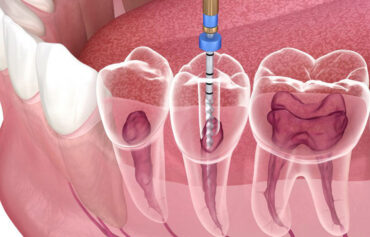

Dr. Patel’s philosophy centersaround providing a patient-first experience, where the highest standards of care are delivered with compassion and precision. She uses advanced tools such as the NSK endomotor, J. Morita apex locator, high-class Vatech X-ray setup, and an in-house dental scanner for accurate diagnosis and treatment. The clinic also specializes in a wide range of dental services, including root canal therapy, wisdom tooth removal, composite fillings, zirconia crowns, E-Max veneers, and much more. For those needing full-mouth rehabilitation, dental implants, or flap surgery, NOVA Dental Hospital offers a comprehensive suite of services with remarkable attention to detail.